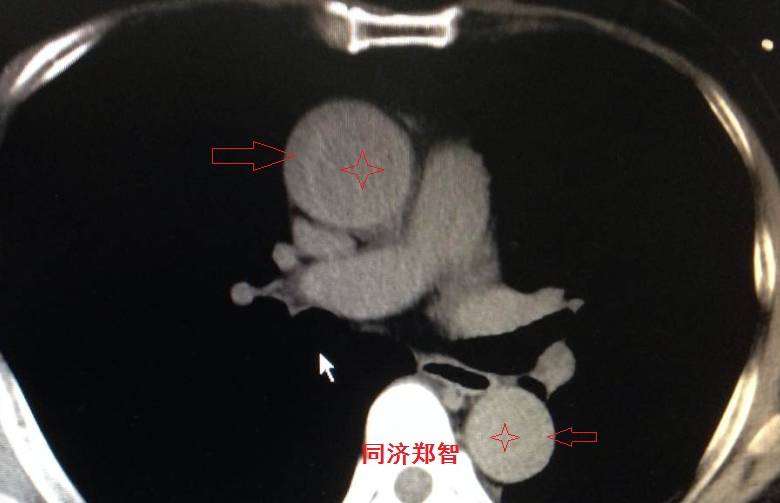

平扫CT提示降主动脉内膜片征,同时内膜片中可见一钙化点。CTA证实为B型主动脉夹层。

病例十

腹主动脉平扫CT提示正常外周一圈的钙化影中有内移的钙化影(红色箭头所示),CTA 证实为腹主动脉夹层